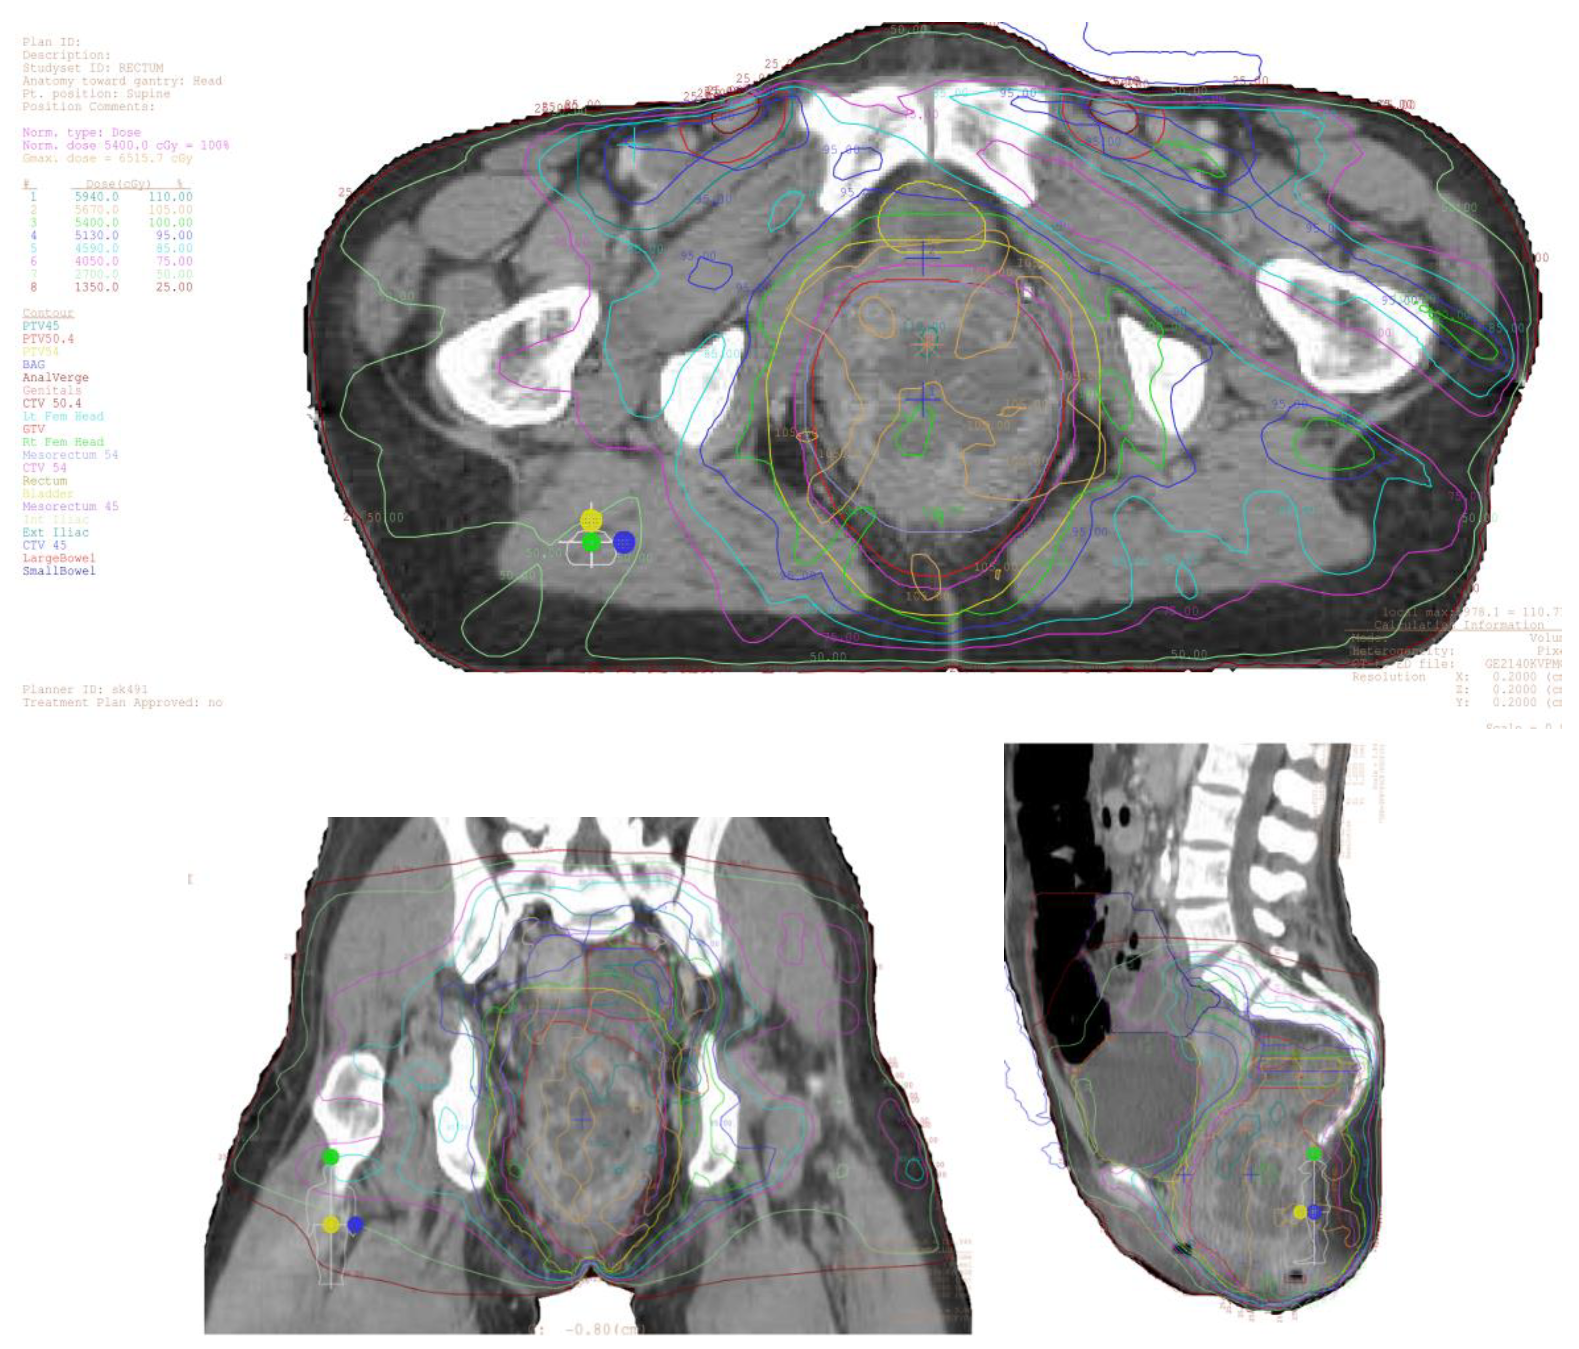

8. Intensity-Modulated Radiation Therapy: RTOG 05-29

10. Treatment Planning and Delivery: Institutional Practice and Recent Advances